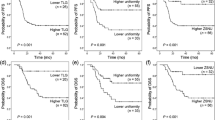

Area under the receiver operating characteristic (ROC) curve (AUC), cut-off values, sensitivity (SEN), specificity (SPE), and diagnostic accuracy for each statistically significant texture parameter with AUC ≥ 0.5 are shown in Tables 4 and 5, respectively. ROC curves are illustrated in Figs. 3 and 4.

Receiver Operating Characteristic (ROC) curve analysis of post-gadolinium T1 images. Upper part of the image: correlation of Grey Level Non-Uniformity feature between patients with residual cancer (positives) and inflammatory edema (inflammation) and between positives and negatives patients. Negative patients are patients with tissue alterations characterized by inflammatory edema or fibrosis. Lower part of the image: correlation of Energy feature between positive and negative patients and between patients with residual cancer (positives) and residual fibrosis (fibrosis). The features showed an Area under the curve (AUC) between 0.7 and 0.8, that is indicative of an acceptable level of discrimination between the two groups of patients

Receiver Operating Characteristic (ROC) curve analysis of Apparent Diffusion Coefficient (ADC) map images of the five features resulted to be statistically significant (Dependence variance, Large Area Emphasis, Large Dependence Emphasis, Run Variance, Zone Variance). The features showed an Area under the curve (AUC) between 0.7 and 0.8, that is indicative of an acceptable level of discrimination between the’positive’ and ‘negative’ patients